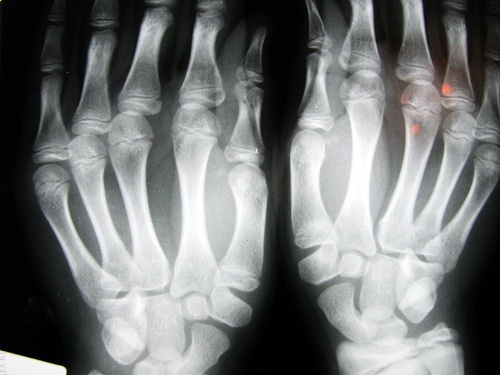

Risco de osteoartrite

Um estudo realizado pela Universidade de Nottingham (Reino Unido) pôde determinar que as pessoas que têm o dedo indicador mais curto que o resto; têm um maior risco de desenvolver problemas como a osteoartrite.

Este problema foi relacionado à falta de estrógenos e à pouca atividade física; que afeta especialmente as mulheres.